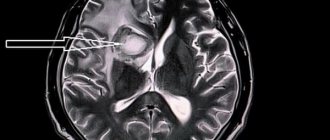

• МРТ мозга. Визуализирует локализацию и размер очага кровоизлияние. В режиме реального времени на мониторе компьютера показываются участки кровопотери и уплотнения паренхимы. На снимках видно, какие отделы головного мозга затронуты, какой сосуд лопнул, затронут ли ствол головного мозга,

• КТ мозга. По результатам диагностируется стадия кровоизлияния. Первая стадия – кровь отсутствует, вторая стадия – кровяные сгустки меньше одного миллиметра, третья стадия – кровяные сгустки больше одного миллиметра, четвертая стадия – кровь попала в желудочки,